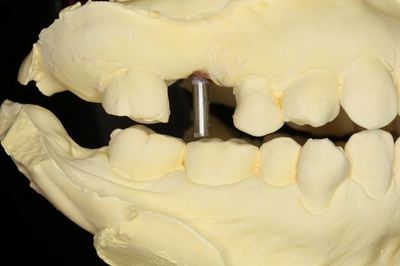

KaVo プロターevo7咬合器にマウントしました。

CTデータと重ね合わせて予定位置・方向に金属棒を植えます。

プラスチックでドリルガイドを作製します。(ライブピンクのレジンに意味はありません)